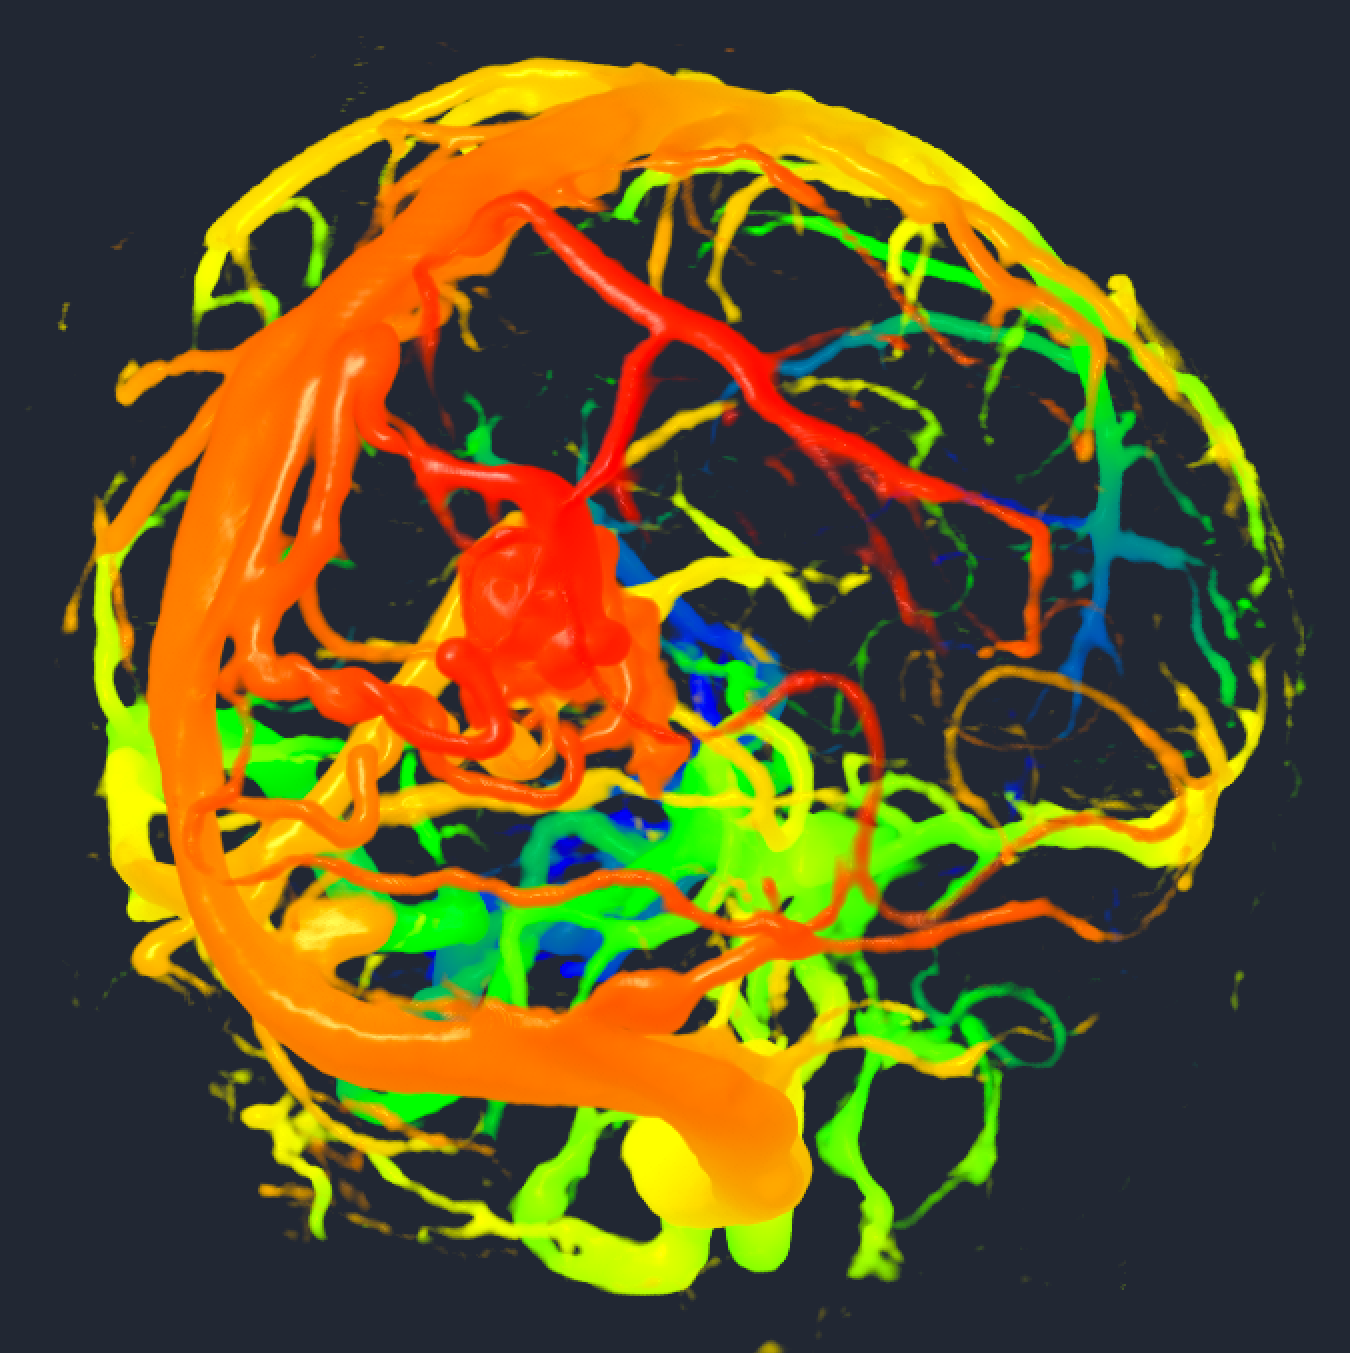

- Provided a proof of concept (python script) for dynamic shader editing in Slicer (see image, video and link to script below)

Proof of concept

Result

Illustrations

| Philips 3D US | Chroma-depth in PRISM | Depth peeling in PRISM |

|---|---|---|

|

|

|

| Edge enhancement in PRISM | Decluttering in PRISM | Volume carving in PRISM |

|---|---|---|

|

|

|

| Blood flow animation in PRISM | ||

|---|---|---|

|